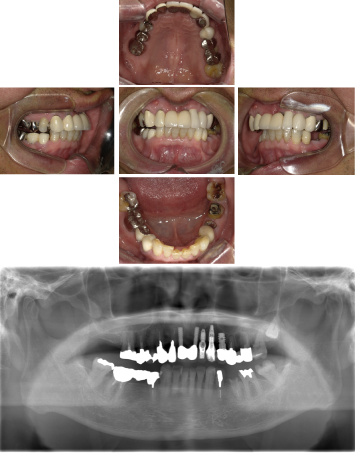

60代 女性 全顎 インプラント サイナスリフト等

| 年代・性別 | 60代・女性 |

| 主訴 | 上顎の入れ歯が割れた。リンゴやおかきを食べられるようになりたい。 |

| 部位 | 右上④3②・左上②3④5⑥のブリッジ |

| 治療期間 | 2年 |

| 費用 | ¥2,447,500(税込) |